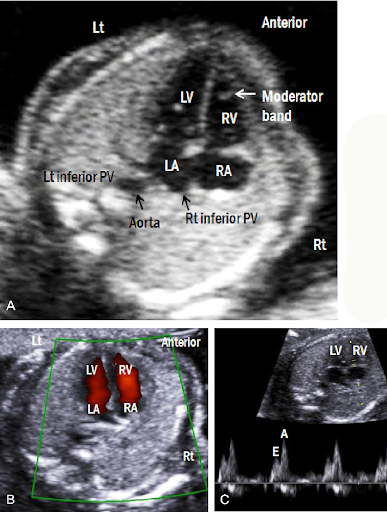

Biophysical profile is a prenatal assessment tool that evaluates fetal well-being using real-time ultrasound and a non-stress test. It measures acute and chronic markers of hypoxia. Components scored include fetal breathing movements, body/limb movements, tone, amniotic fluid volume, and non-stress test. A normal score is 8–10. Normal amniotic fluid index (AFI) is 8–24 cm; normal single deepest pocket is 2–8 cm.

Rationale for correct answers

1. Fetal breathing movements are assessed by ultrasound; at least 1 episode of rhythmic breathing lasting ≥30 seconds in 30 minutes is normal.

3. Fetal movement is part of the BPP; ≥3 discrete body or limb movements within 30 minutes indicates normal activity.

4. Amniotic fluid volume reflects chronic uteroplacental function. A single vertical pocket ≥2 cm or AFI ≥5 cm is normal.

5. Non-stress test evaluates fetal heart rate accelerations with movement. Normal is ≥2 accelerations of ≥15 bpm lasting ≥15 seconds in 20 minutes.